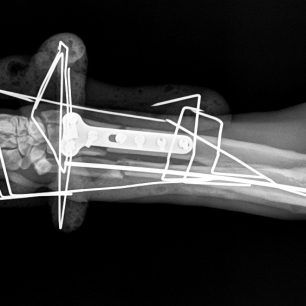

Η κα Μακρή δημοσίευσε σήμερα στο facebook την γνωμάτευση του κτηνιάτρου σχετικά με την εξέλιξη της υγείας του ζώου. Σε αυτή αναφέρεται ότι: «Ο σκύλος έφερε συντριπτικά ενδοαρθρικά κατάγματα με μετατόπιση στο κάτω τρίτο του αριστερού αντιβραχίου και στο κάτω τρίτο του αριστερού μηριαίου. Ολοκληρώθηκε με επιτυχία η πρώτη χειρουργική επέμβαση που αφορούσε την ανάταξη και οστεοσύνθεση του αριστερού αντιβραχίου. Λόγω της σοβαρότητας του κατάγματος η διάρκεια της χειρουργικής επέμβασης ήταν 4 ώρες και 25 λεπτά και ο σκύλος ανένηψε φυσιολογικά».